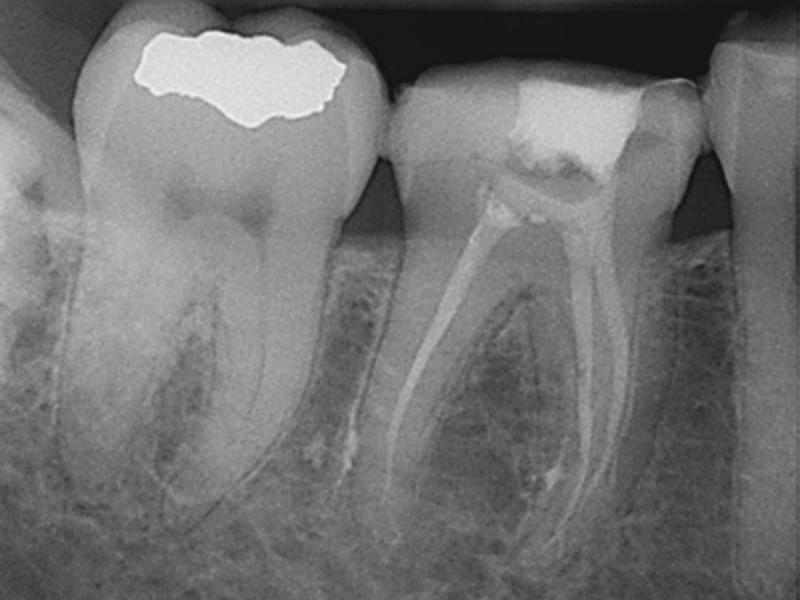

Post-Op